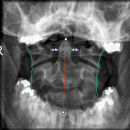

- 1) Exakte Aufnahmetechnik? - Projektion korrekt?

- 2) Atlantoaxialer Übergang: Distanz Dens-Massa lateralis ? (Distanz 3-5mm = V.a. parteielle Ruptur des Lig transversum; Distanz > 5mm = V.a. komplette Ruptur des Lig. transversum)

- 3) Konturlinien überprüft: Laterale Konturlinien, Dornfortsatzlinien

Beurteilung von

- Atlas

- Axis mit Dens axis

- Atlantoaxialgelenk